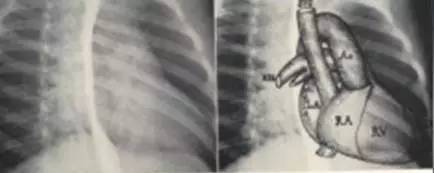

右前斜位(rao)

右前斜位 自后前位向左转45-60°,应作食道吞 钡

左心房增大 右 前 斜 位 食管受压后移

右前斜位片示意图

右前斜位心脏的示意图